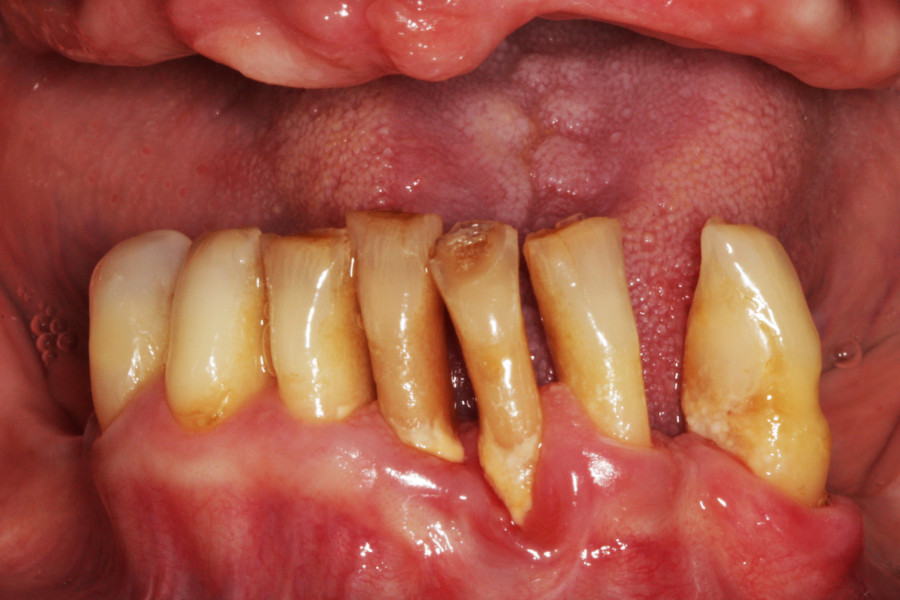

Pacjentka lat 65, zgłosiła się do stomatologa na konsultację, ponieważ niepokoiła ją ruchomości zębów. W pierwszej kolejności została skierowana na wizyt higienizacyjną. Bezzębie w łuku górnym zaopatrzone było całkowitą akrylową protezą, w łuku dolnym pacjentka nie użytkowała żadnego uzupełnienia. Pacjentka niepaląca.

Postępowanie rozdzielono na dwie wizyty. Badaniem klinicznym, oceniając wskaźniki periodontologiczne, uzyskano wartości API 100%, PBI 100% świadczące o konieczności poprawy higieny i procesie zapalnym dziąseł, duże złogi kamienia nad i poddziąsłowego, bardzo obfity biofilm, pogłębione wszystkie kieszonki dziąsłowe, ciężkie zapalenie dziąseł, ruchomości zębów dolnych III stopnia, duży zanik kości. Badanie kliniczne błony śluzowej jamy ustnej nie wykazało zmian patologicznych.